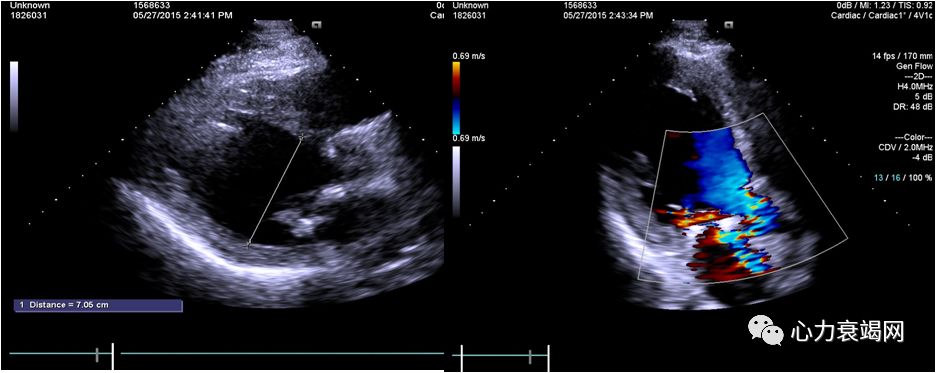

➤ 全心扩大(左房内径50mm,左室内径(d)76mm,(s)58mm)

➤ LVEF47%,肺动脉压94mmHg

➤ 二尖瓣前叶收缩期突向左房,二尖瓣收缩期见重度关闭不全

➤ 室间隔厚11mm,左室后壁厚11mm

➤ 心脏超声:

1.二尖瓣前叶裂缺伴中重度反流

2.左房室增大

3.左室下壁及前壁收缩活动减弱

4.轻度肺动脉高压

➤ 术中经食道超声心动图检测提示:二尖瓣腱索断裂伴重度反流